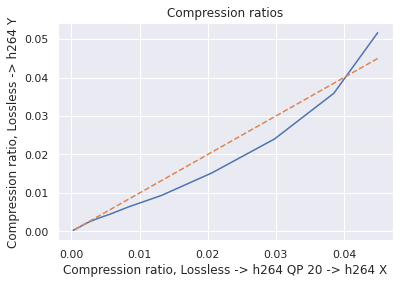

Since our dataset was compressed to be transferred from hospitals, we first investigated the impact of multiple stages of compression ("generation loss"). We used lossless video (24 seconds, 1.4GB) collected from an endoscope viewing dyed, non-human tissue. This gave the video the motion and texture characteristics of a colonoscopy. We then compared video quality between two compression schemes: compressing using H264 QP , where , and compressing to H264 QP20, then to H264 QP (when referring explicitly to this comparison, we will concisely refer to the latter as ’QP’). We then compared the average frame quality between these two schemes using two quality metrics (see ’Metrics’ section). The quality differences between these two compression schemes was minor in terms of PSNR-CbCr, which justifies our working with video data already compressed by H264 QP20.